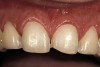

Figure 2  Note the invisibility of the marginal line in the completed veneers, even though the margin has not been carried below tissue.

Figure 2